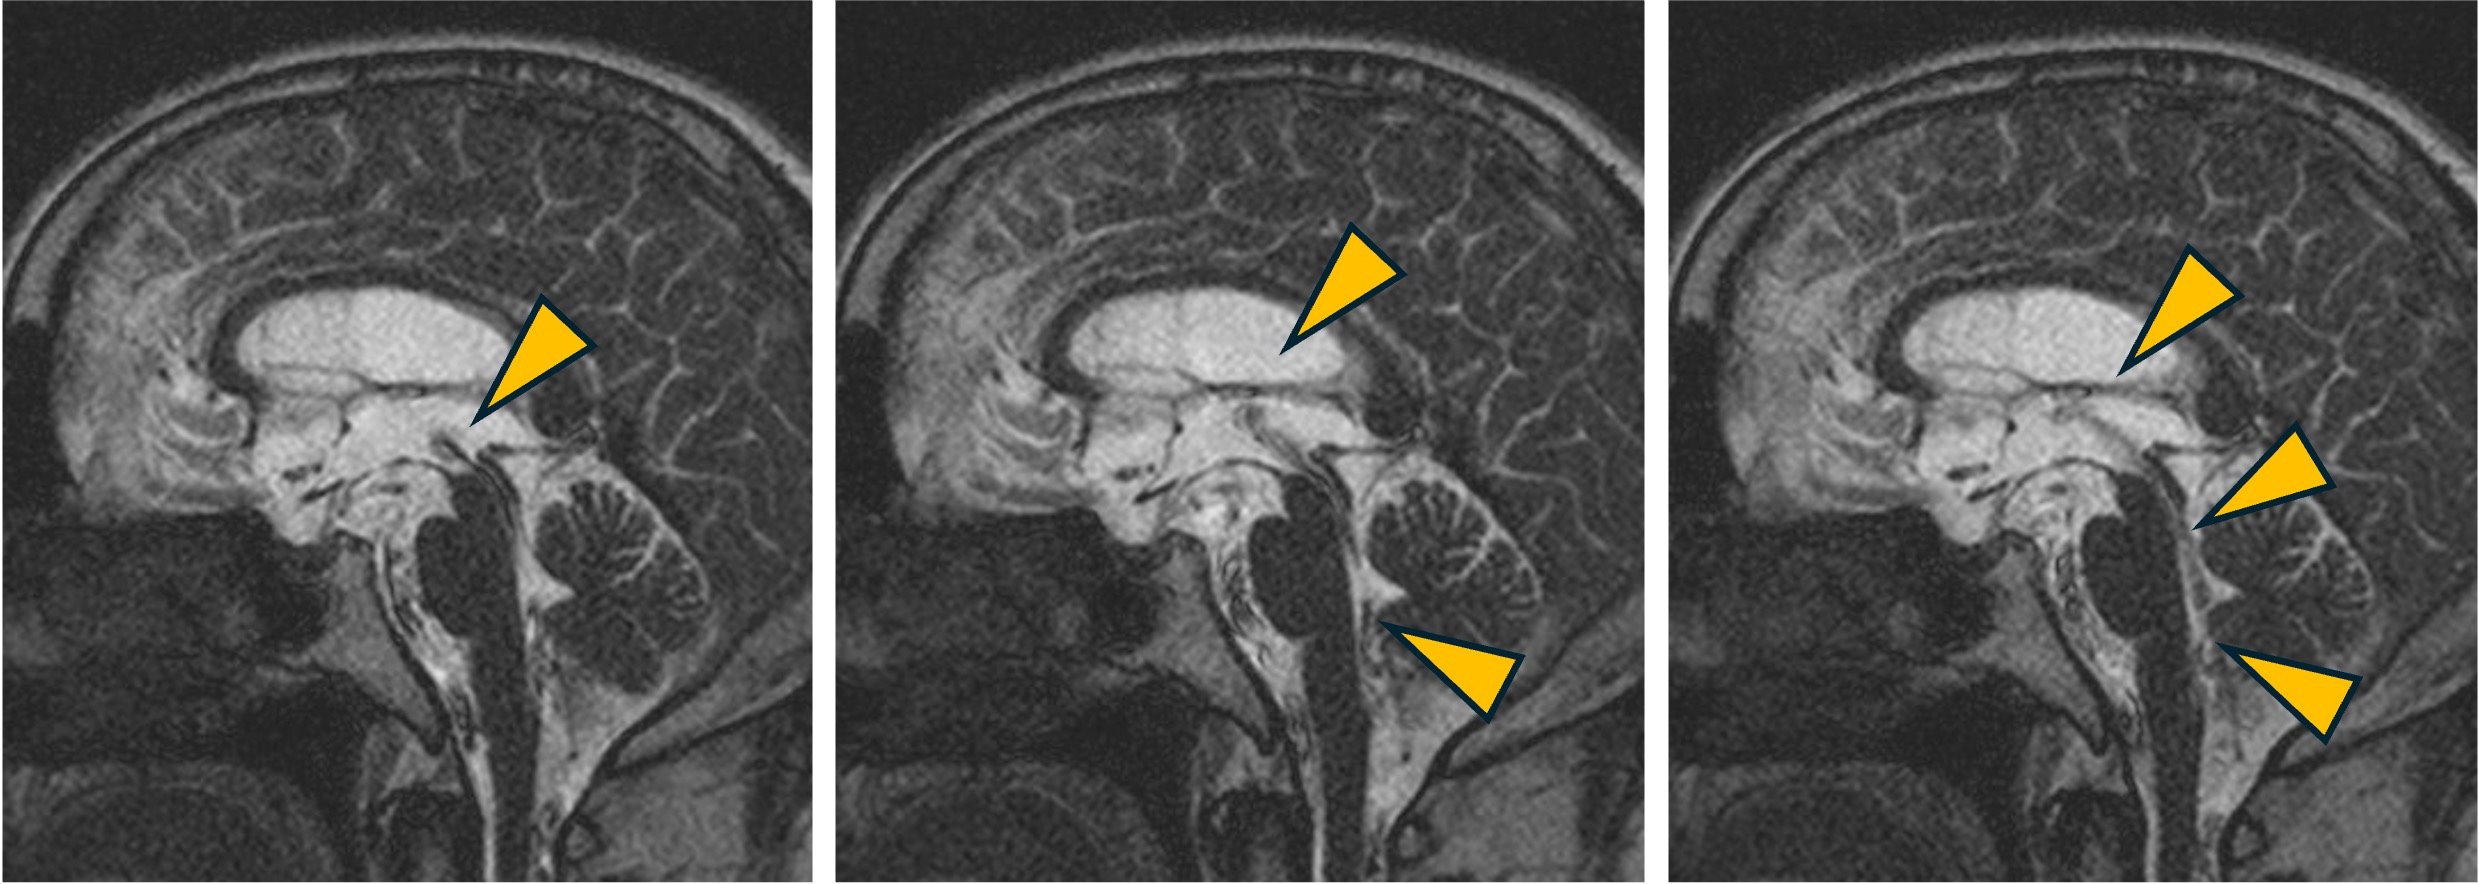

PSIF-CINE imagingによるCSF flow症例。

第3脳室〜第4脳室にかけての髄液の拍動性流動が明瞭に確認できます。